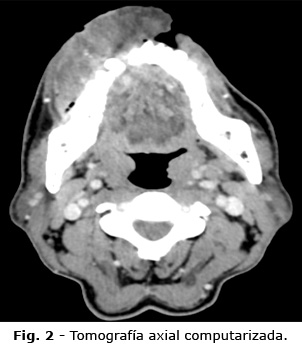

Los hallazgos en la tomografía computarizada mostraron una masa del labio inferior y espacio bucal derecho, con invasión de la cortical ósea del maxilar inferior, por el reborde alveolar y cortical vestibular, adyacente a los dientes 42, 43 y 44, e invasión de la mucosa yugal y del carrillo derecho (Fig. 2).